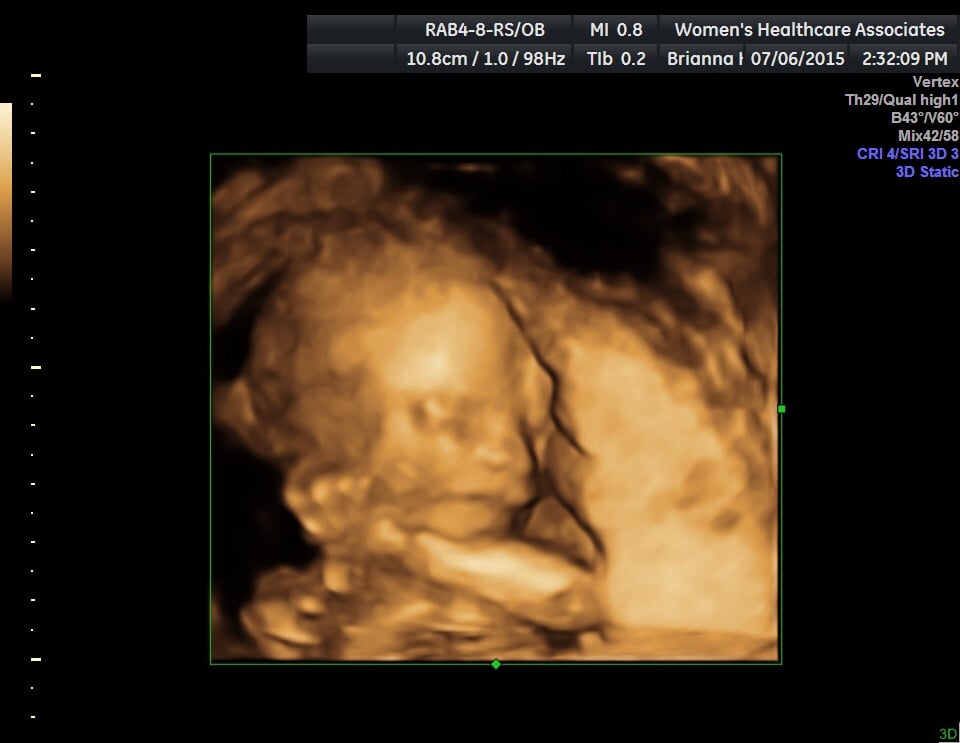

Congrats @missphilippine !!! Looks like your babe is suckling their thumb.